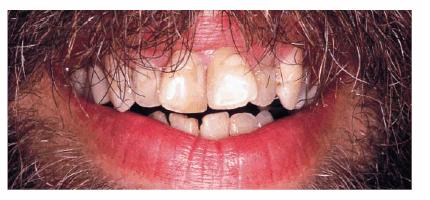

PROBLEM: This 38-year-old store owner presented with crowded and

discolored maxillary and mandibular teeth (Figures 24-7A, and 24-7B). Although orthodontic treatment was suggested as ideal

treatment, he elected a compromise that consisted of bonding the mandibular and

crowning the maxillary teeth.

Figure 24-7A: This 38-year-old man wanted to improve his crowded maxillary and mandibular teeth.

Figure 24-7B: This occlusal view shows why full orthodontic treatment was originally presented as the ideal treatment. The patient insisted on a "quick fix" solution.

TREATMENT: When teeth are as crowded as this, it is sometimes necessary

to do a vital pulp extirpation to prepare the teeth for adequate porcelain

thickness. Thus, tooth preparation and diagnostic wax-up were first completed

on the study casts (Figures 24-7C, and 24-7D). The patient was fully informed of the possibility of

endodontic therapy. The actual tooth preparation can be seen in Figures 24-7E, and 24-7F. Fortunately, the pulp had receded, so extirpation was

not necessary. Electrosurgery was completed prior to impressions to improve

access to the preparation margins. Six full porcelain crowns restored the

esthetics of the maxillary arch (Figure 24-7G), whereas composite resin bonding helped restore

mandibular esthetics. A maxillary occlusal night appliance was constructed for

the patient to wear since the patient had a history of clenching while

sleeping.

Figure 24-7C: Diagnostic casts show the extent of crowding in the maxillary anterior teeth.

Figure 24-7D: A wax-up was completed to demonstrate to the patient and dental team how crowns could be used to accomplish the esthetic goal.

Figure 24-7E: Although the patient was warned that endodontic therapy might be necessary on the maxillary incisors, the teeth were prepared without pulpal exposures.

Figure 24-7F: The occlusal view shows the patient ready for impressions after electrosurgery for effective tissue displacement.

Figure 24-7G: The final six crowns show improved proportion and symmetry in the arch.

RESULT: The resulting smile with straighter and lighter teeth (Figures 24-7H, and 24-7I) was most appreciated by the patient.

Figure 24-7H: Pretreatment smile.

Figure 24-7I: Post-treatment smile with six maxillary full porcelain crowns and four mandibular incisors with bonded composite resins.